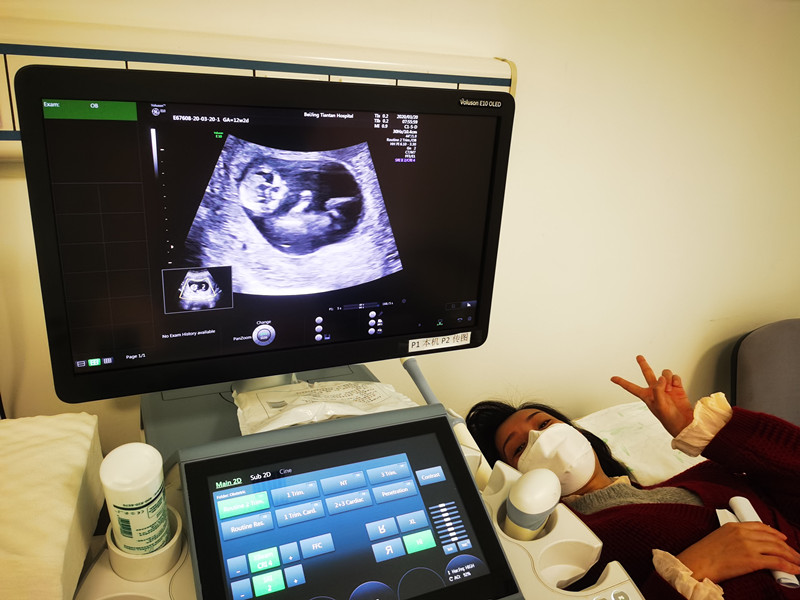

“你看,这是他的头,这是小手,还在动……”3月20日,是北京支援武汉医疗队在武汉工作的第54天,来自北京天坛医院的队员袁磊第一次通过B超影像,见到了自己的宝宝。

医院各级领导对支援武汉医疗队队员和家人的生活十分关心,特别安排护理部人文关怀小组组长苏娅丽等全程照顾。早上8点,杜晓彤在母亲的陪伴下来到北京天坛医院超声科,安静地躺在检查床上。随着超声科副主任医师王立淑的操作,显示屏上,一个小小的胎儿形象清晰地显示出来。

“袁磊,看看你们家宝宝,可爱吗?”苏娅丽用手机拍摄下显示屏上的画面,伸手、踢腿、翻身,这个87天的小生命似乎听到了外面的召唤,用各种动作回应大家的召唤,每一个动作都会引起大家的笑声。检查室里只有躺在床上的杜晓彤看不到屏幕,一脸茫然。

“咚”,设备里传来一声清晰的胎心跳动,大家被这个新生命所震撼和感动,瞬间安静下来,感情丰富的人已经红了眼眶。

终于做完检查,杜晓彤看到了视频中宝宝的影像。看着画面里“精神抖擞”的小生命,这个坚强的母亲笑着笑着,泪水夺眶而出。

“今天是第一次看见他,他的小脑袋、小手、小脚,一直在动,特别活跃。我特别紧张,特别激动。在武汉这么多天,他一直就是我的牵挂,今天终于看到他,虽然还看不清他的样子,但是已经感受到他的活力。我觉得这是在武汉最好的礼物。”袁磊说。他叮嘱爱人:“照顾好自己,照顾好宝宝,好好吃饭好好睡觉,踏踏实实等我回家。”